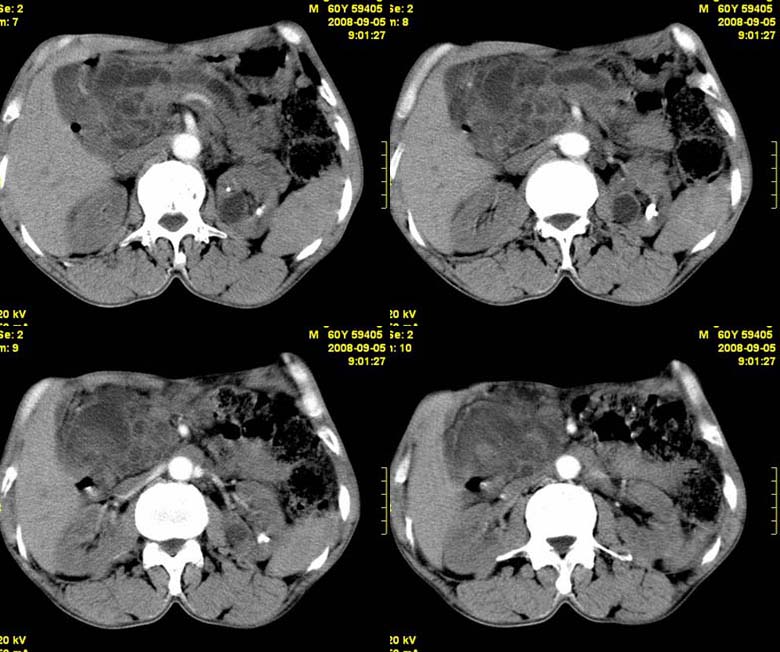

标题: CT15580:M60Y,胰腺病变,平扫+增强 [打印本页]

标题: CT15580:M60Y,胰腺病变,平扫+增强

患者,男, 60,既往有间歇腹痛病史多年,现右上腹痛,加重一月,伴右后背部疼痛,无黄疸,无发热。

胰头区增大,胰管明显扩张,不均匀强化,且与 周围结构不清,后背疼痛,考虑为胰腺头部胰腺癌。

胰头囊腺癌。

胰腺囊腺瘤可能性大,囊腺癌不除外.

同意胰头部囊腺癌。

胰头囊腺癌可能性大。

结合病史考虑慢性胰腺炎伴脓肿形成。

胰腺囊腺癌/慢性胰腺炎,建议查肿瘤标志物。